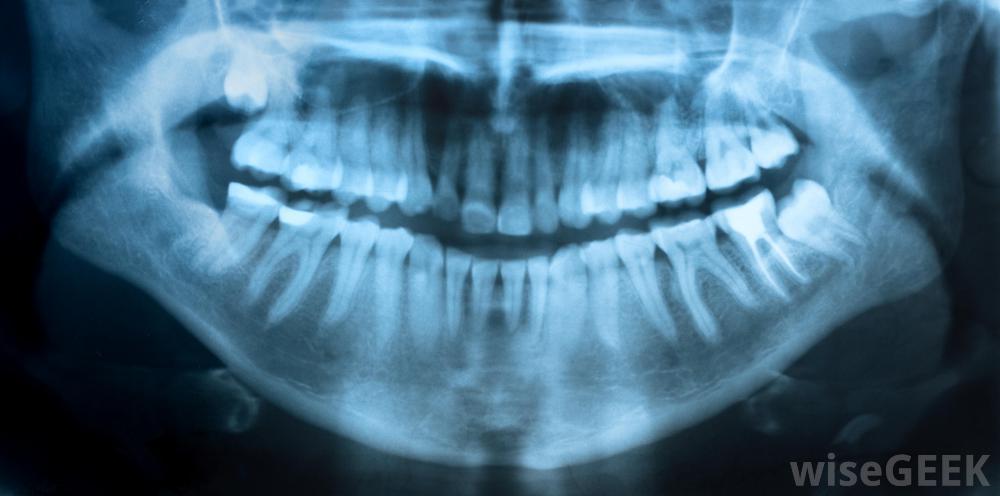

有些牙齿问题是通过x光片检测出来的。一般来说,有些人需要在较长的时间内摄入10倍于每日推荐摄入量的氟化物,氟斑牙通常出现在骨骼形态之前,这可以让医务人员及早发现问题。过量的氟化物可能来自氟化物污染,吸入含氟粉尘和烟雾、大量含氟水、补充剂、过度饮用茶叶,氟中毒可导致我食用含氟牙膏氟斑牙以牙齿上的小斑点和小斑点开始,有时伴有牙釉质的轻度透明如果病情继续恶化,牙齿会变得麻点、开裂和易碎。如果发现氟斑牙,患者通常会接受有关氟化物来源的教育,以便他或她能够学会避免氟化物,牙齿可能会出于美观的原因进行贴面或封盖,以保护牙齿免受进一步损害

在8岁之前摄入过多的钙会损害牙釉质。氟中毒的骨骼形式会导致骨骼脆性以及关节疼痛。由于骨骼不易观察到,而且其他情况也会导致类似的问题,因此很难确定。在世界上氟中毒流行的地区,这些症状通常被视为患者患有该病的迹象,而在这种情况较为罕见的地区,要弄清问题的真相可能需要一段时间。有时,x光可以用来显示骨骼。